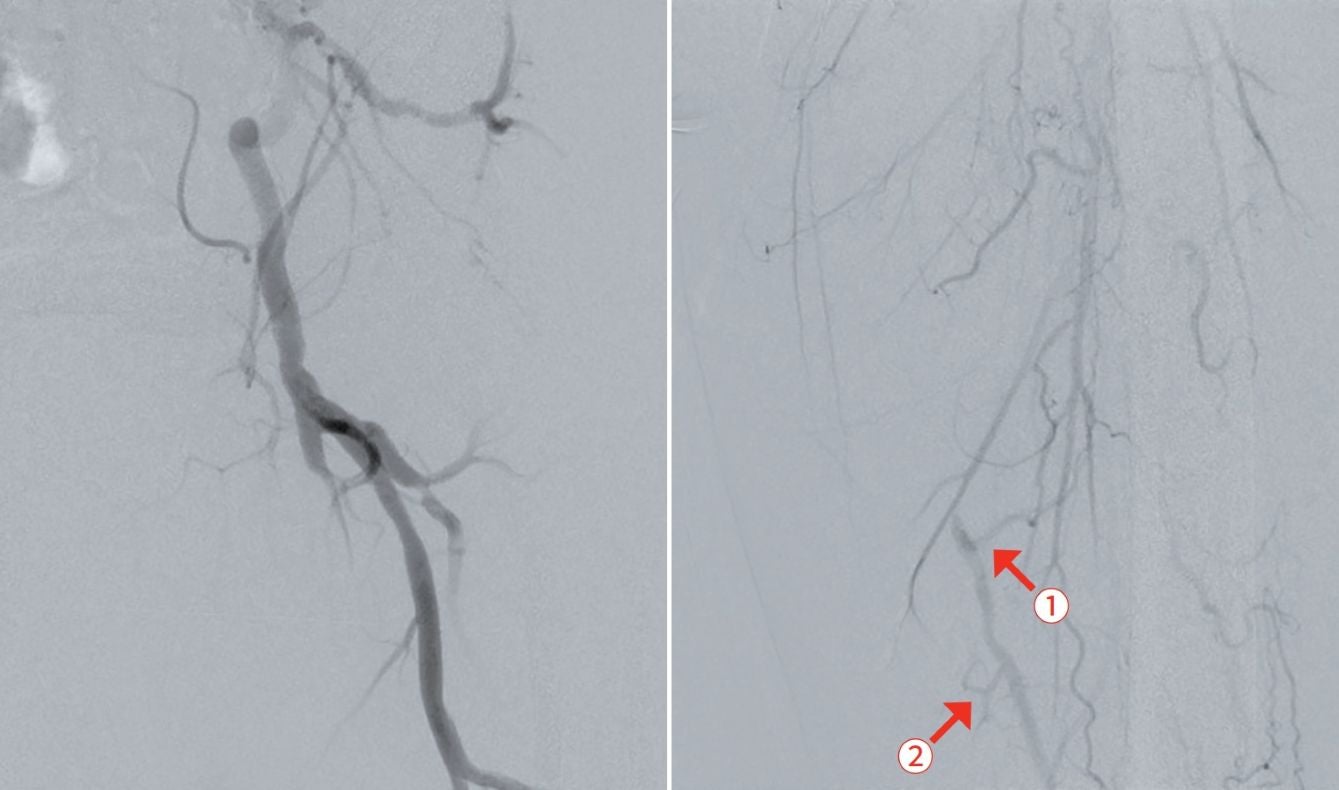

当症例は、20 cmを超える浅大腿動脈長区域病変(図1)である。一般的に、バルーンでの拡張後の解離が修復できなかったり、プラークの圧着が不充分な場合には、ステントなどのスキャフォルドが必要になる。治療当時はベアメタルステントの成績も期待が持てず、薬剤溶出型ステント(DES)の成績も未知数であったが、ゴア® バイアバーン® ステントグラフトに関しては、唯一20 cm以上の病変長でも適応があり、25 cmまでの長区間病変での成績1,2も発表されているので、成績に期待が持てた。

当症例の悩ましいポイントは、バイアバーン® ステントグラフトの適切な留置時ポイントの一つがヘルシーランディングを行うことであるが、造影上CTO病変遠位部に発達したコラテラル血管があり、そのコラテを温存してバイアバーン® ステントグラフトをヘルシーランディングできるかどうかであった。

当院では、通常IVUSと造影で閉塞部両端のプラークの少ない健常部と思われる部分をマーキングし、ヘルシーランディングのポイントをIVUSを用いて確認している。この時、メジャーを貼っておいて位置確認に使用すると位置のずれを気にせず作業できる。当症例では、コラテ(図1矢印①)を温存しながら、ヘルシーランディングを行う戦略とし、前拡張を行うこととした。また、IVUSで計測された血管径から至適と思われるサイズ(遠位健常部の血管径が一つの目安になる)のバルーンにて前拡張を行うことにしており、バルーンの径サイズは遠位健常部の血管径に合わせると余計な解離なく拡張できると考え、また、バイアバーン® ステントグラフトを使用する場合には、5 mm以上のバルーンサイズで拡張できるか検討することにしている。さらに、200-300 mm長のロングバルーンで1-2回の長時間拡張(当院では3-5分)を行うと期待する拡張が得られやすいと考えており、当症例では、径6.0/長300 mm セミコンプライアントバルーンで前拡張を行った。

前拡張後の造影で温存したいコラテ部分に解離が認められ(図2)、また、IVUSでヘルシーランディングが可能な位置を確認したところ、遠位部のコラテ(図1矢印②)を温存してヘルシーランディングができることを確認できた。さらにIVUSで血管径を確認し、同等サイズのバイアバーン® ステントグラフトを留置した。バイアバーン® ステントグラフトが展開し始めた後、展開ラインをゆっくり連続した動作で引くようにするとバイアバーン® ステントグラフトの位置がずれることなく留置することが可能であった。その後、バイアバーン® ステントグラフト全長を同径のバルーンで高圧後拡張してIVUSでバイアバーン® ステントグラフトが充分拡張されていることを確認し、手技を終了した。(図3)